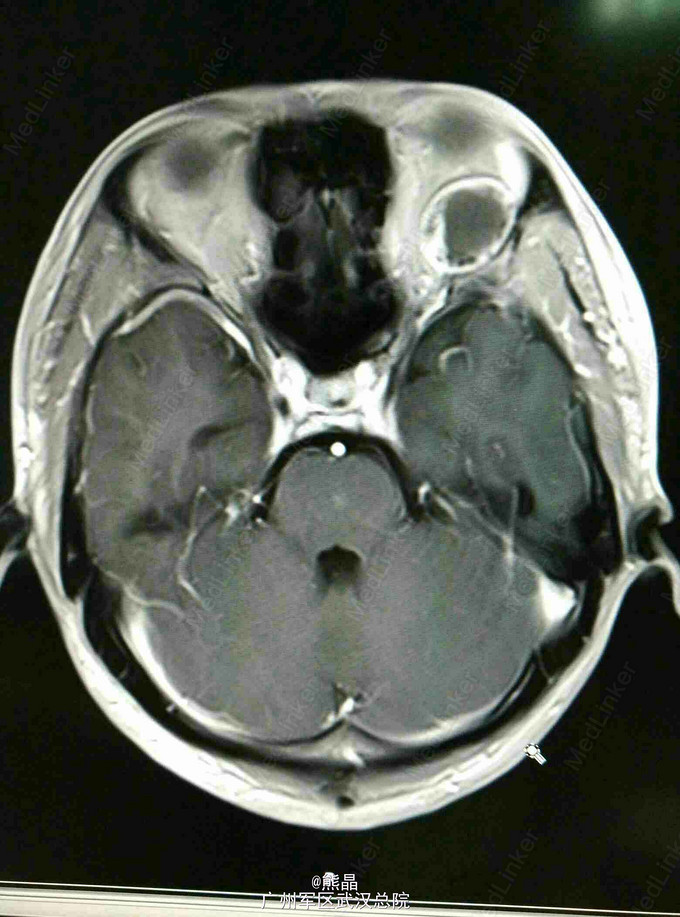

左眼眶神经鞘瘤的MRI表现一例

男性患者,27岁,左眼球突出2月余

MRI表现:左眼眶内球后肌锥内可见一椭圆形等T1长T2信号,内可见液平,增强呈斑片状强化,余未见明显异常

本院手术,术后病理,神经鞘瘤